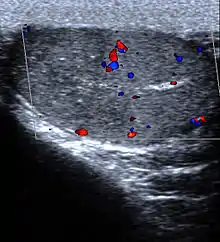

| Micrograph of a pulmonary infarct (right of image) beside relatively normal lung (left of image). H&E stain. | |